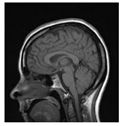

| Original Image | Marked Image | Encrypted Image (DRPE) | Decrypted Image | Correlation between Extracted Blocks and Original Blocks |

![]() | ![]() PSNR = 34.26 dB SSIM = 0.96 | ![]() PSNR = 12.84 dB SSIM = 0.0349 | ![]() PSNR = 34.37 dB SSIM = 0.96 | ![]() |